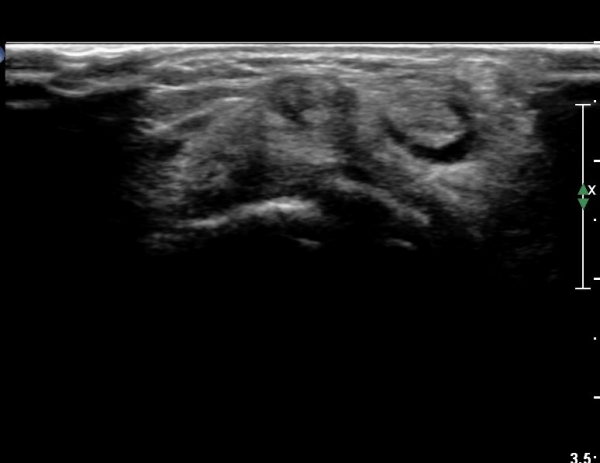

¼Õ¸ñ µî Áß¾Ó¿¡¼­ ¼Õ°¡¶ô ½ÅÀü°Ç Á¾´Ü¸é °Ë»ç¿¡¼­ ƯÀÌ ¼Ò°ßÀ» º¸ÀÌÁö ¾Ê´Â´Ù(»çÁø 1)